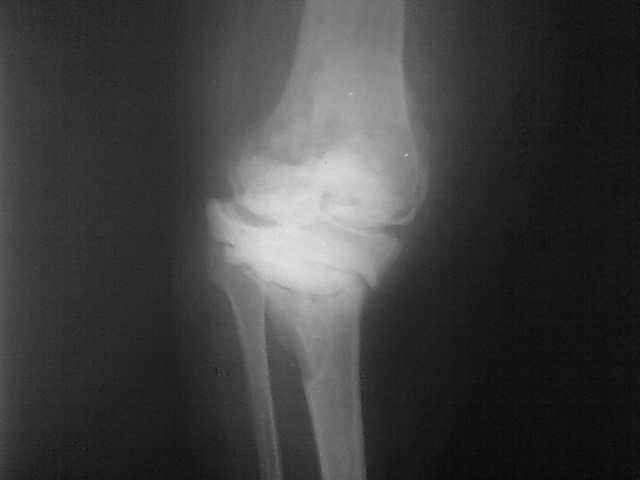

Женщина 1952 г.р., оперирована в 2006, в одной клинике установлен эндопротез правого коленного сустава, через год нестабильность обоих компонентов, доктор выполняет ревизию обычным протезом с задним стабилизатором.

В октябре 2008 - нестабильность, свищ. В другом стационаре все удалено, спейсер с гентамицином, длинный курс антибиотиков.

Коллатеральных связок нет. Собственная связка надколенника цела.

До удаления протеза - выраженная смешанная контрактура.

Планы: Стоит выбор 1) Обычный hinge с цементными ножками, вставками под тибиальным и бедренным компонентами с импакционной костной пластикой аллокостью с применением сеток для удержания трансплантата на tibia; 2) Онкологический hinge - с замещением проксимальной голени и сохранением бедра; 3 - артродез.